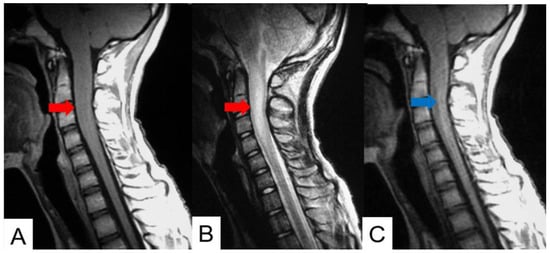

Schwannomas usually show low intensity in T1-weighted MR imaging and high intensity in T2-weighted MR imaging (Figure 1 and Figure 2). These tumors often enlarge alongside the nerve root and become a dumbbell-type [34]. The heterogenicity of a tumor indicates cystic change.

Figure 2.

Fifty-five M, spinal schwannoma. (A) Enhanced T1-weighted midsagittal image, (B) T2-weighted midsagittal image, and (C) enhanced T1-weighted axial image at C2/3. Red arrow indicates tumor and blue arrow shows tumor enhancement. The tumor is dumbbell-shaped (black arrow).